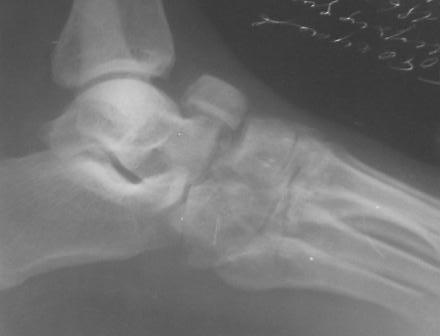

[Ortho] Застарелый вывых ладьевидной кости стопы

Правильные снимки.

По  данному  случаю,  оказалось  3  месяца  назад  было  произведена Р-графия в  райбольнице,  но  больной предпочел  лечится  у  табиба. Присылаю  первичные  снимки.